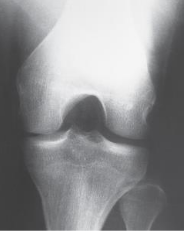

Projection?

AP Medial Oblique knee

Limb is medially rotated how many degrees for an ap oblique medial rotation

45 degrees

Margin of patella projecting slightly

beyond medial side of the femoral condyle

AP Oblique Knee Medial Rotation